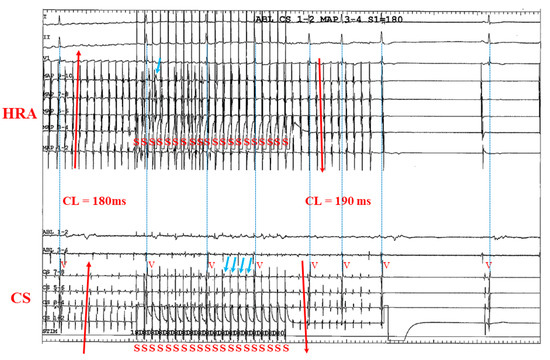

3.2. Representative Cases

3.2.1. Case 1: 42-Year-Old Man with Symptomatic PAF

3.2.2. Case 2: 72-Year-Old Man with Symptomatic PAF

3.2.3. Case 3: 67-Year-Old Man with Symptomatic PAF